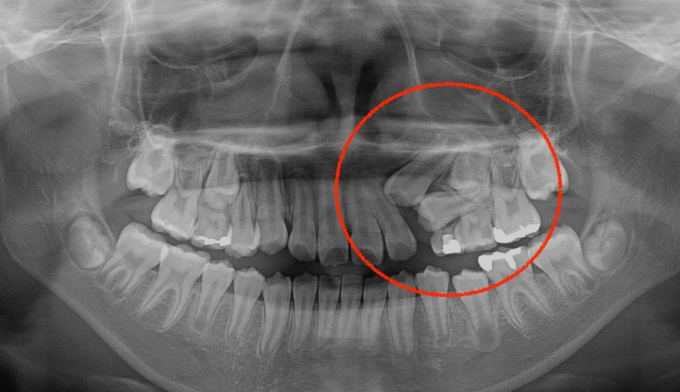

유치를 제때 뽑아주지 못하면 치아 맹출 순서가 뒤죽박죽이 되면 잇몸 안에서 맹출하지 못하게 됩니다.

본 케이스처럼 아예 치아의 각도가 누워버린 경우에는 억지로 교정장치를 부착하여 치아를 제 위치로 당겨주어야 합니다.

잇몸의 일부를 절개하여 교정장치 부착후 치아를 견인하였고 총 치료기간은 16개월입니다.

잠깐의 고생이지만 살려놓은 치아는 평생쓸 수 있는 자산입니다.